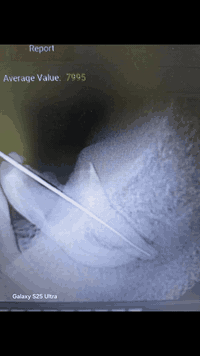

هاي صور السن العقل🤳🤳

مراجعتنا زارت اغلب العيادات ورفضو يعالجون السن🦷🦷

الحل الوحيد القلع

بس عند مركز الرواسي ماكو شي مستحيل 👌👌

تم علاجه باحدث الطرق 👌🧑‍🔬